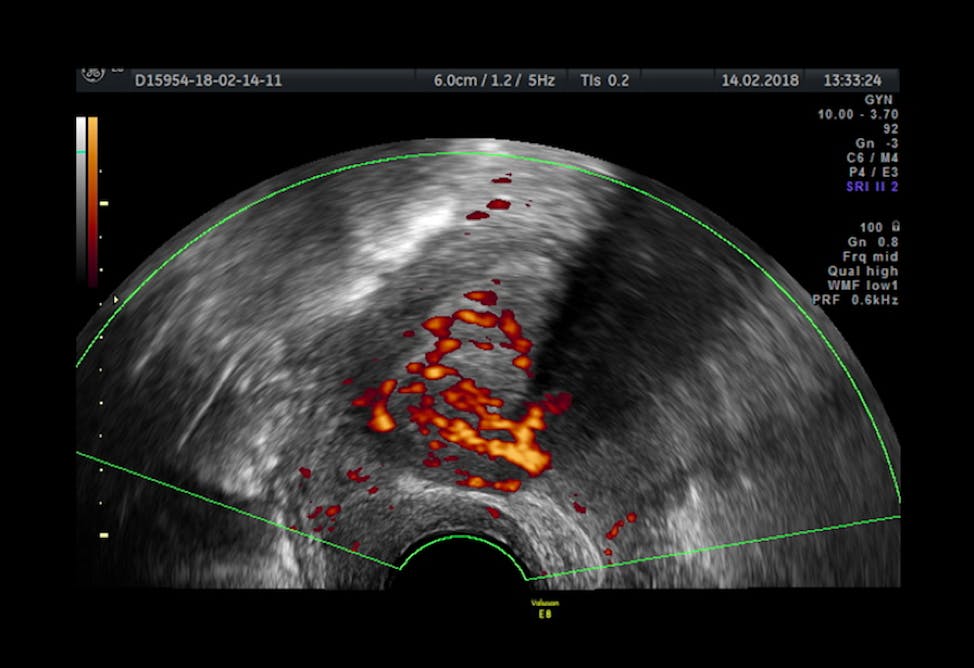

Uterine Cancer Symptoms Treatment from www.clevelandclinic.org Emboly of the mesenteric vessels 3. The risk is increased in women who menstruate longer than average, women who began puberty early, women who have never given birth, and women who start menopause late. Endometrial cancer is more common in developed countries where the diet is high in fat. Invasive neoplasms of the female pelvic organs account for almost 15% of all risk factors for uterine leiomyosarcomas may include early menarche, late menopause, and african american race. A small number of women who have cancers earlier in life, such as. Menopause after cancer can present either immediately or within months or years of treatment. Atherosclerosis, thrombosis of mesenteric vessels 2. Uterine cancer means endometrial cancer or uterine sarcoma.